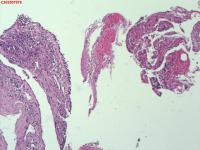

右肺上叶开口处 气管镜咬检

性别

男

年龄

65岁

临床诊断

一般病史

肺TB

标本名称

大体所见

右肺上叶开口上缘处可见肉芽增生,予咬检。

感觉:炎性纤维组织增生